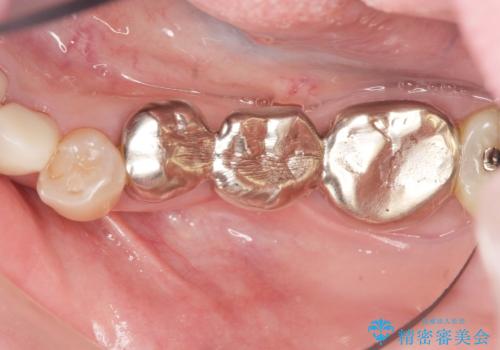

- 笑った時に大きく見えてしまう奥歯の銀歯ブリッジを白くしたいと希望され来院されました。

強度があり、審美性にも優れるジルコニアブリッジに置き替えていく治療計画としました。

- 39.6万円(ジルコニアクラウン×3・仮歯×3)費用は治療当時の料金となります